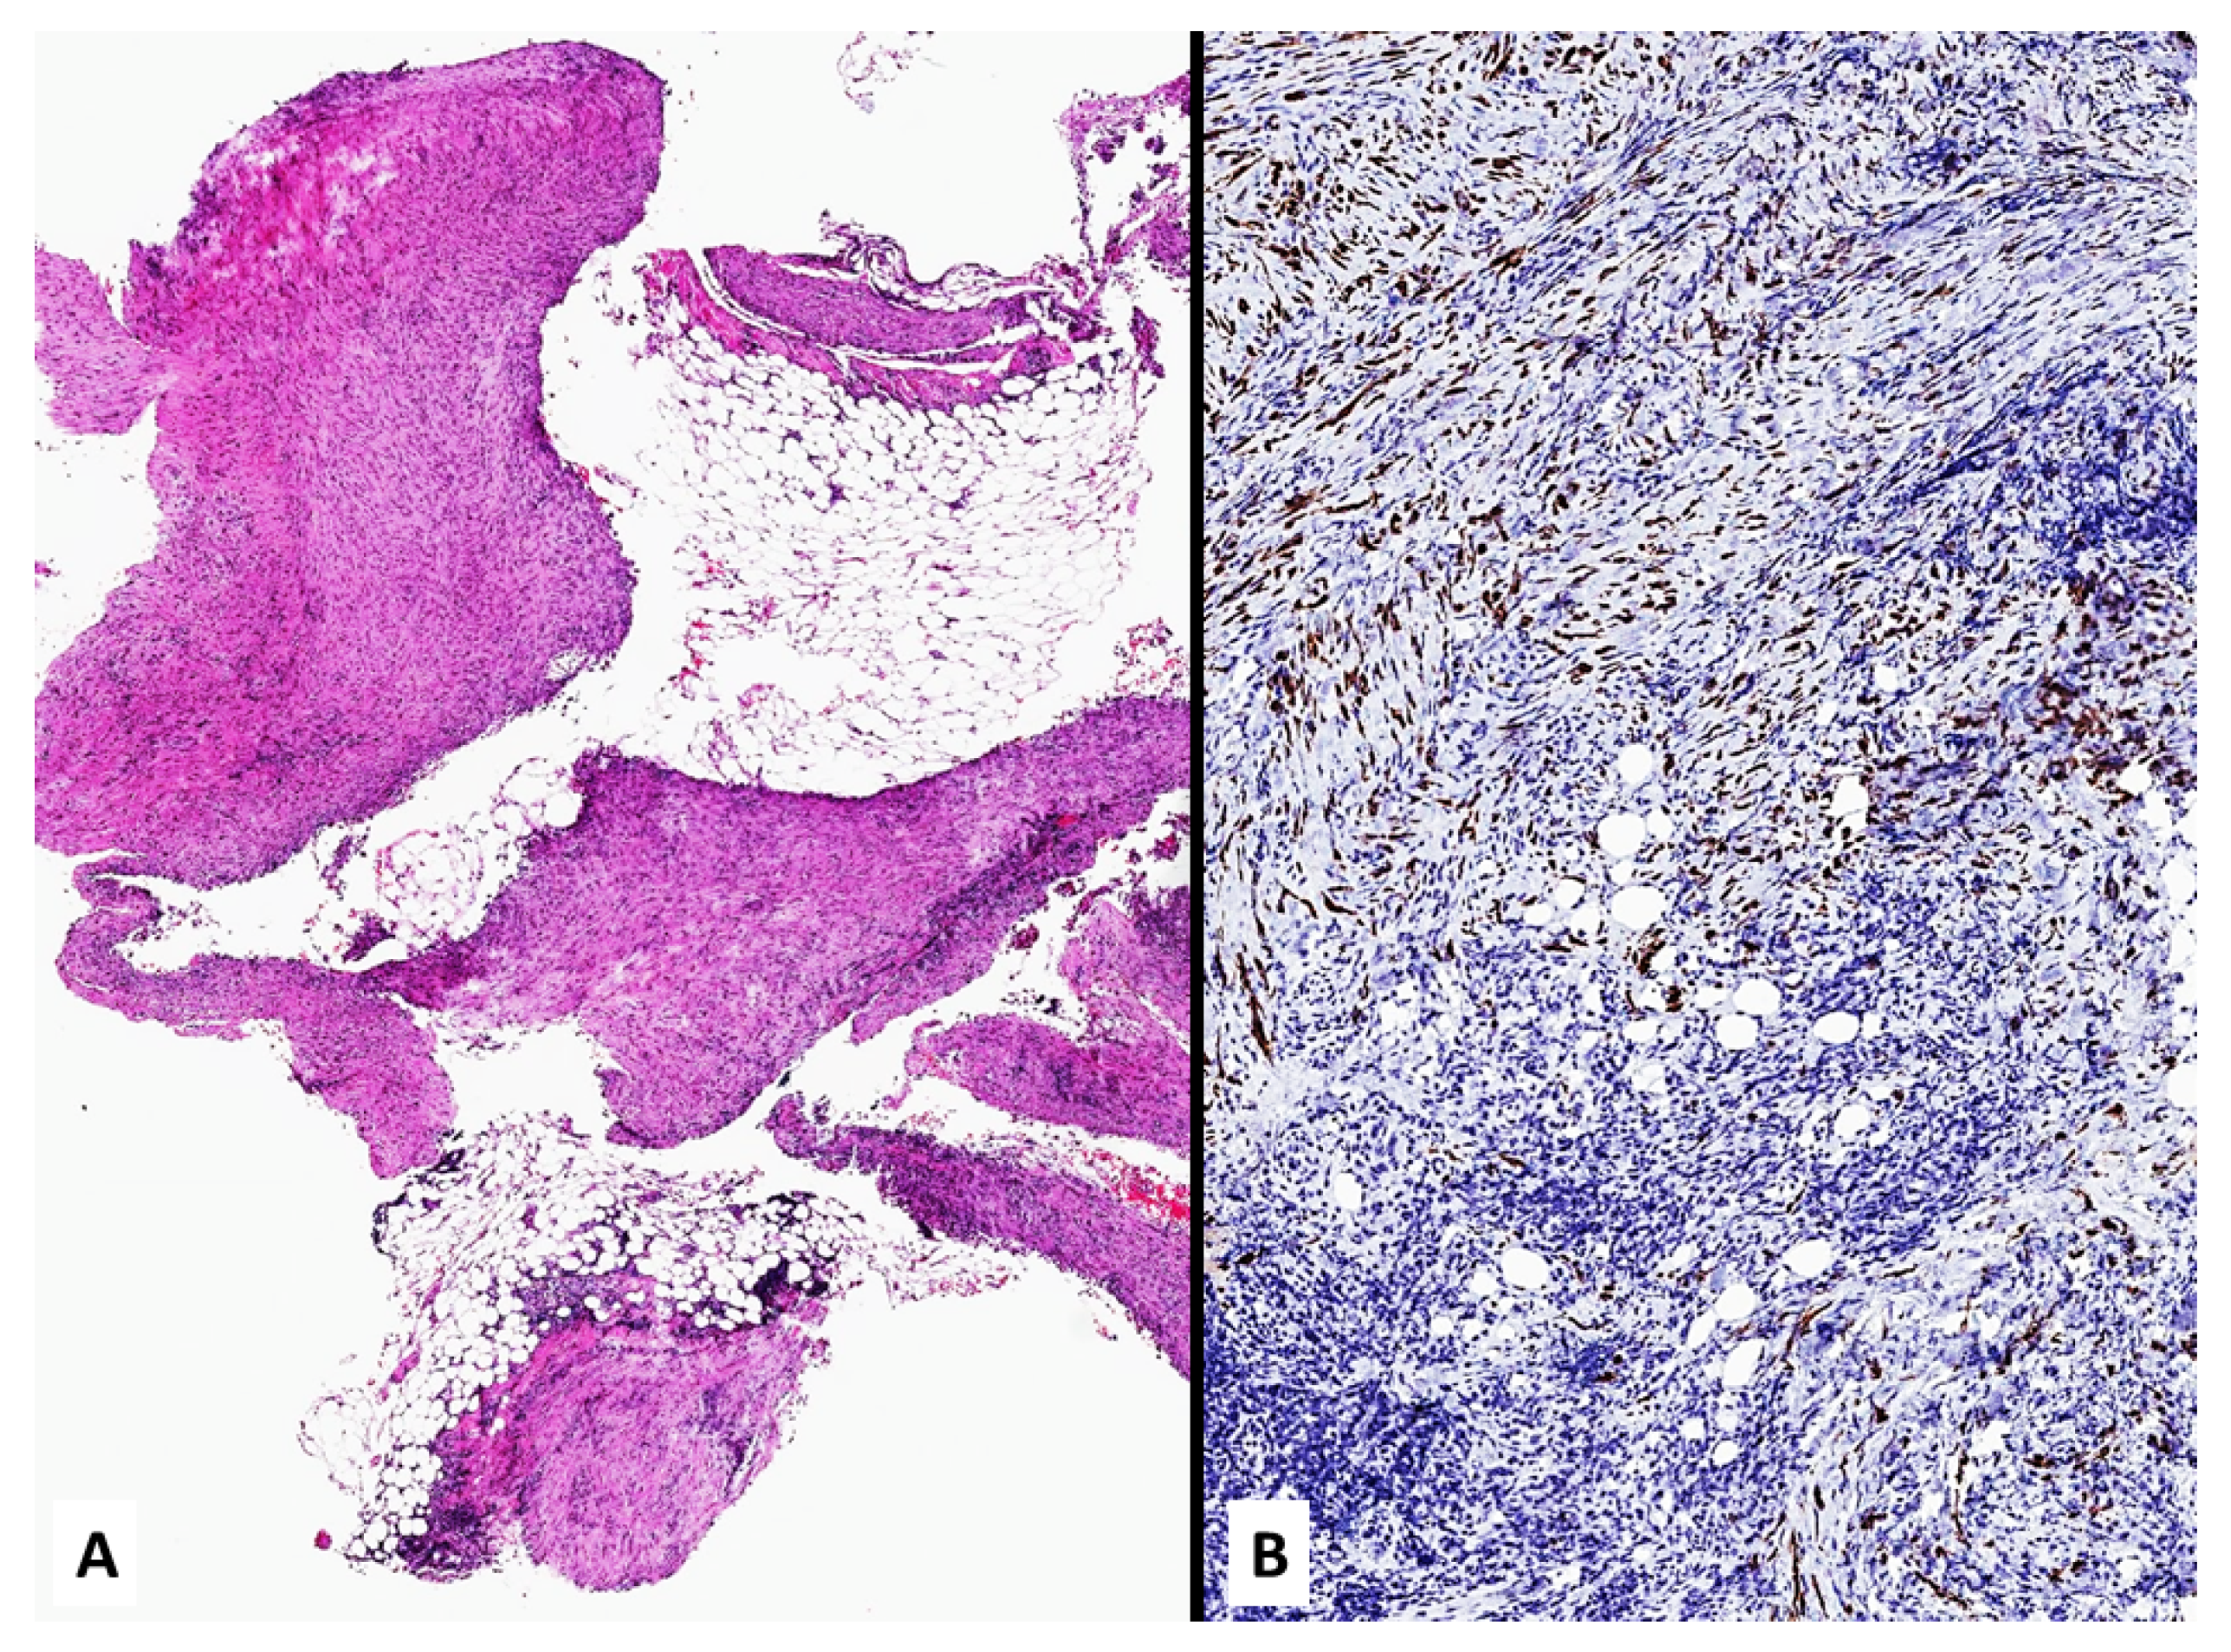

2.1. Mesothelioma in Patients without Definite Asbestos Exposure

4. Unusual Morphologic and Immunohistochemical Features